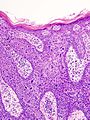

Bowen disease

Bowen disease is squamous cell carcinoma in situ of the skin.

- Its histomorphologic appearance may be similar to Paget disease of the breast/Extramammary Paget disease, Toker cell hyperplasia and melanoma.

- IHC is used to separate the entities definitively.

Micro

The sections show hair bearing skin. The squamous epithelium has full thickness changes including an increased nuclear-cytoplasmic ratio, loss of polarity, and nuclear hyperchromasia. Mitoses are seen in the upper third of the epithelium. Nucleoli are not apparent. No atypical cells are seen in the dermis. Parakeratosis overlies the abnormal keratinocytes. Solar elastosis is present. No melanocytic nests are identified.

Alternate

The sections show hair bearing skin. The squamous epithelium has full thickness changes including increased nuclear-cytoplasmic ratio, nuclear enlargement, loss of polarity, and nuclear hyperchromasia. Mitotic figures are easily identified.

No atypical cells are seen in the dermis; however, the epidermis is thickened. The dermal epidermal interface has a smooth contour. No paradoxical differentiation is identified. Inflammation at the dermal epidermal junction is minimal. Parakeratosis overlies the normal keratinocytes. The lesion is completely excised in the plane of section. Dermal scarring is present.